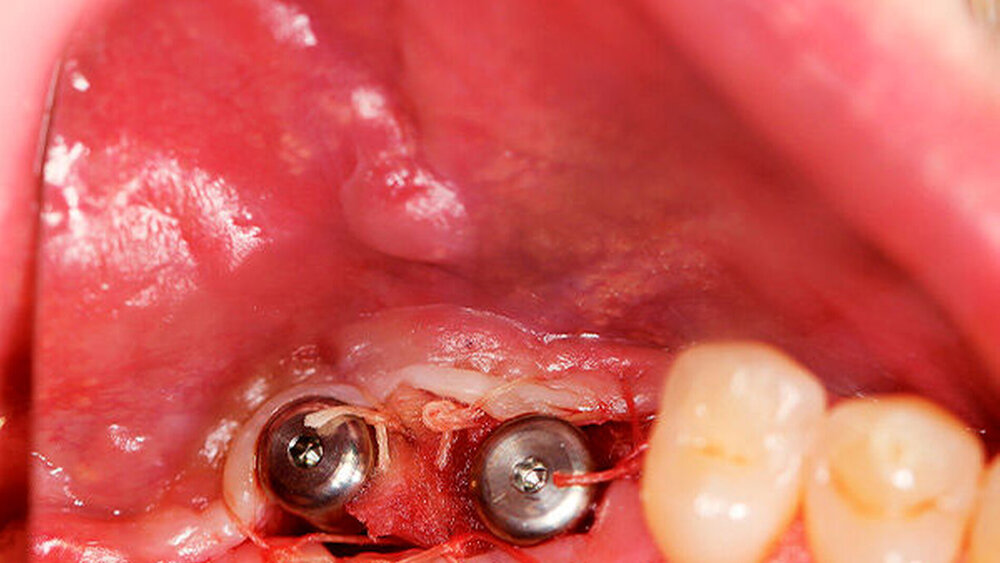

Die Schnittführung wurde nach dem Pillar-Sockel-Design (Blume) vorgenommen. Dabei liegt die Inzision weit im Vestibulum und verbindet zwei vertikale Entlastungsschnitte. Im Gegensatz zu der herkömmlichen krestalen Schnittführung bleibt das Periost über dem augmentierten Bereich damit völlig intakt. Nach der streng subperiostalen Präparation erfolgte die Kontrolle der Passung des CAD/CAM-Blocks. Ein ganz entscheidender Punkt ist, vor jeglichem Kontakt des Blockes mit Blut diesen in steriler Kochsalzlösung und am besten in der PRF-Flüssigkeit zu wässern, sodass sich keine Poren des Blocks mit Blutkoageln verschließen und innerhalb des Blocks ein nicht mit Blut gefüllter Hohlraum bildet. Vor der Befestigung des Blocks wurde die Kompakta des Empfängerbetts mit einer kleinen Kugelfräse mehrfach perforiert um sogenannte Bleeding Points zu setzen, die die Durchblutung des Knochenblocks gewährleisten. Mit zwei Osteosyntheseschrauben mit dem Durchmesser 1,5 mm und der Länge 9 mm wurde der allogene Knochenblock rotationssicher fixiert. Das Augmentat wurde mit einer dünnen Schweinepericard-Membran (Jason membrane, botiss biomaterials GmbH, Vertrieb Straumann) und der PRF-Membran abgedeckt. Der spannungsfreie Wundverschluss erfolgte mit der modifizierten vertikalen Matratzennaht nach Laurrell mit resorbierbarem Nahtmaterial (Vicryl 4.0). Postoperativ wurde ein Oberkiefer-DVT angefertigt. Die Nahtentfernung wurde im Rahmen der Nachsorgeuntersuchung sieben und 14 Tage postoperativ vorgenommen. Nach einer Heilzeit von sechs Monaten erfolgte die Implantation in Lokalanästhesie unter antibiotischer Abschirmung mit 2 g Amoxicillin oral eine Stunde präoperativ. Die Schnittführung erfolgte krestal, und nach subperiostaler Präparation wurde der Knochenblock dargestellt und die Osteosyntheseschrauben wurden entfernt. Danach wurden drei Implantate (Straumann) in den Knochenblock gesetzt und mit 0er-Verschlussschrauben abgedeckt. Die Wundrandadaptation erfolgte mit resorbierbarem Nahtmaterial, das bei der Verlaufskontrolle sieben Tage postoperativ vollständig entfernt wurde. Nach dreimonatiger gedeckter Einheilung wurden die Implantate im Rahmen einer Vestibulumplastik freigelegt. Dafür wurde eine erneute krestale Schnittführung regio 14 bis 17 vorgenommen und ein Splitflap präpariert. Der vestibuläre Wundrand wurde mit Einzelknopfnähten im Vestibulum fixiert. Im Bereich der Implantate wurde der Splitflap perforiert, um die Abdeckschrauben gegen Gingivaformer auszutauschen, und der Bereich des nun freiliegenden Bindegewebes wurde mit einer 3D-vernetzten Kollagenmatrix (mucoderm, botiss biomaterials GmbH, Vertrieb Straumann) abgedeckt. Diese wurde zunächst gewässert, um die Verarbeitung zu erleichtern, und an den Stellen der Gingivaformer gestanzt. Die Nahtentfernung erfolgte neun Tage postoperativ. (Abb. 1a bis 1f).

Ein 29-jähriger Patient stellte sich mit einer massiven Alveolarkammatrophie im rechten Unterkiefer in unserer Praxis vor. Diese lag in langen Jahren der Zahnlosigkeit begründet. Eine Beckenkammaugmentation kam für den Patienten nicht in Betracht. Dennoch wünschte er die Versorgung mit festsitzendem Zahnersatz. Nach ausführlicher Beratung entschied sich auch dieser Patient für eine Augmentation mit einem patientenindividualisierten allogenen CAD/CAM-gefertigten Knochenblock. Die DICOM-Daten des Unterkiefer-DVTs wurde an die Firma Zimmer gesendet, und es erfolgten wie im oben beschriebenen Fall eine virtuelle Planung und das virtuelle Design des allogenen Knochenblocks anhand der geplanten Implantatpositionen. Nach der üblichen Kontrolle und Freigabe des Chirurgen erfolgte die eigentliche Fertigung und Übersendung des Knochenblocks in die Praxis. Die Augmentation erfolgte auch in diesem Fall in Vollnarkose unter antibiotischer Abschirmung perioperativ mit Ampicillin. Die Schnittführung im Unterkiefer unterscheidet sich von der Sockelschnittführung im Oberkiefer aufgrund der Anatomie (N. mentalis). Auch bei diesem Patienten wurde eine tief im Vestibulum liegende bogenförmige Inzi‧sion durchgeführt, jedoch ohne die vertikalen Entlastungen. Nach streng subperiostaler Präparation erfolgte die Darstellung des N. mentalis. Die Vorbereitung des Spenderbetts sowie die Wässerung, Einpassung und Befestigung des allogenen Knochenblocks gestalteten sich wie im Fallbeispiel 1. Die Heilzeit des Knochenblocks dauerte ebenfalls sechs Monate. Zwei Implantate (Straumann) wurden nach krestaler Schnittführung in Lokalanästhesie eingebracht und heilten subgingival binnen drei Monaten ein. Aufgrund des massiven Volumenzuwachses war auch ebenfalls eine Vestibulumplastik im Zuge der Implantatfreilegung notwendig. Das Prozedere verlief ebenfalls wie im Fallbeispiel 1. Das freiliegende Gewebe wurde mit einer Kollagenmatrix abgedeckt. Dadurch konnte die Breite der befestigten Gingiva deutlich verbreitert werden.